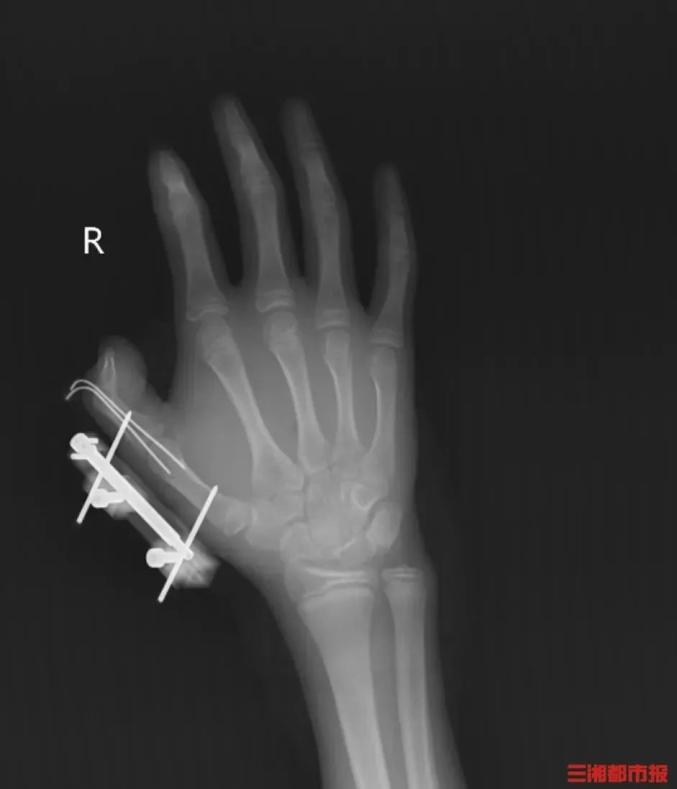

突然,密封袋里的干冰发生爆炸,维维右手瞬间鲜血直流,拇指虎口处被撕开一道约10厘米的伤口,深可见骨,肌肉组织断裂外露,还伴随着拇指骨折、关节脱位,整个拇指完全失去知觉。

见状,家人赶紧带他到当地医院包扎,随后紧急转往湖南省人民医院手足显微外科。经治疗,维维的拇指保住了,但后续还需长期康复训练,才能慢慢恢复手部精细动作功能。